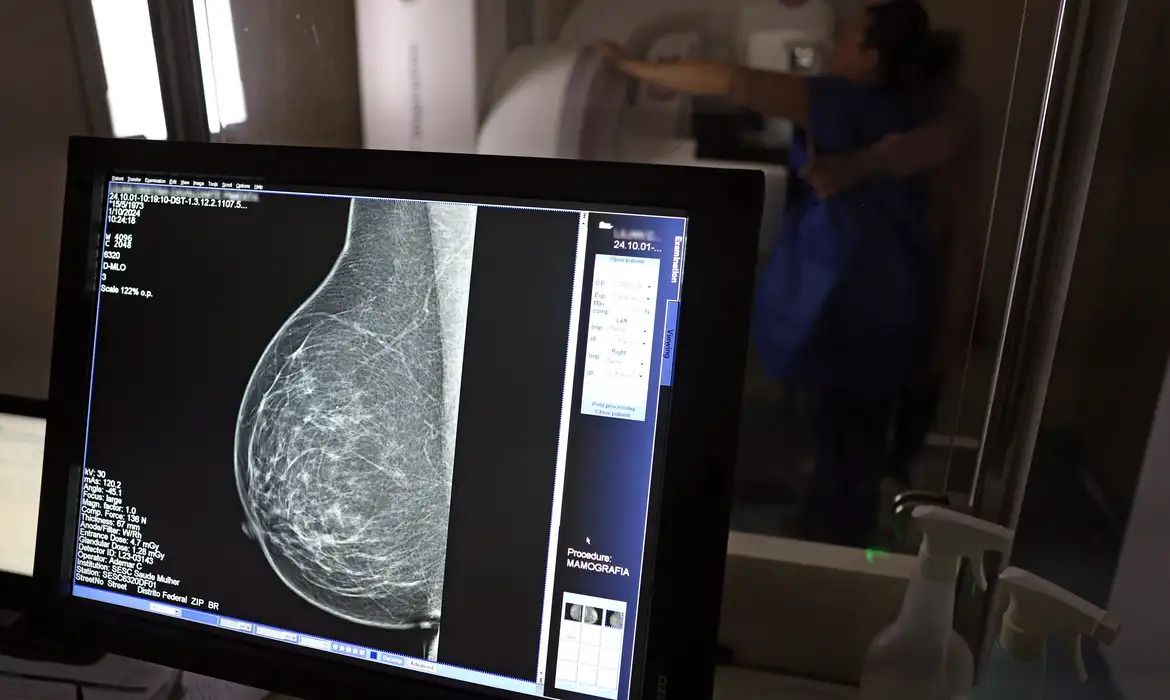

No Outubro Rosa, o Instituto Nacional de Câncer (Inca) estimou 73.610 novos casos este ano no país. É o câncer que mais mata mulheres no Brasil. As mulheres em tratamento pela doença têm o direito de receber o auxílio-doença ou o benefício de prestação continuada.

A vice-presidente da Comissão de Previdência Social Pública da Ordem dos Advogados do Brasil do Rio de Janeiro (OAB-RJ), Danielle Guimarães, destaca que o câncer de mama é uma das doenças que mais afetam mulheres no Brasil, impactando não apenas a saúde física e emocional, mas também a capacidade de trabalho e a segurança financeira das pacientes.

Segundo Danielle, o auxílio por incapacidade temporária, conhecido como auxílio-doença, destina-se a seguradas que ficam temporariamente incapacitadas para exercer suas atividades profissionais devido ao câncer de mama ou aos efeitos do tratamento (cirurgias, quimioterapia, radioterapia e seus efeitos físicos e emocionais).